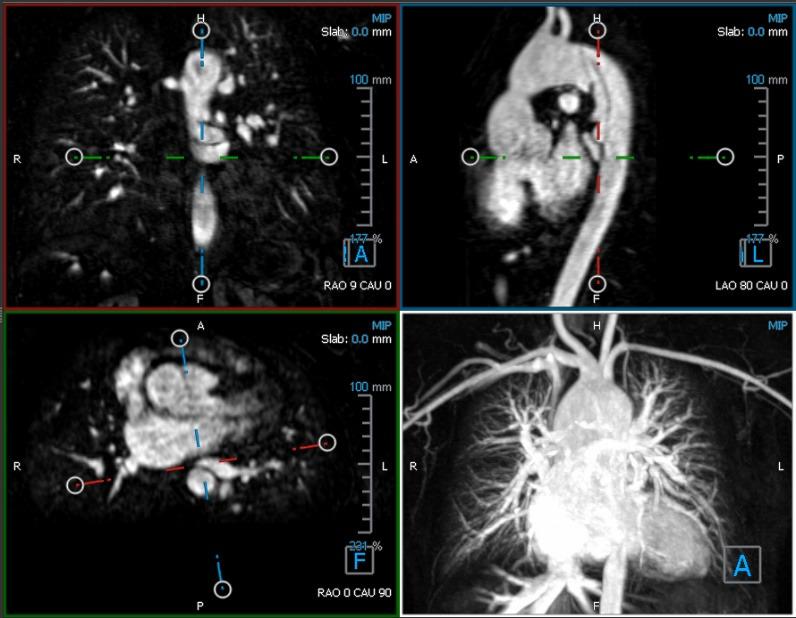

The complex 3-dimensional (3D) nature of anatomical abnormalities in congenital heart disease (CHD) necessitates multidisciplinary group discussions centered around the review of medical images such as magnetic resonance imaging. Currently, group viewings of medical images are constrained to 2-dimensional (2D) cross-sectional displays of 3D scans. However, 2D display methods could introduce additional challenges since they require physicians to accurately reconstruct the images mentally into 3D anatomies for diagnosis, staging, and planning of surgery or other therapies. Virtual reality (VR) software may enhance diagnosis and care of CHD via 3D visualization of medical images. Yet, present-day VR developments for medicine lack the emphasis on multiuser collaborative environments, and the effect of displays and level of immersion for diagnosing CHDs have not been studied.

A total of 22 medical trainees consisting of 1 first-year, 10 second-year, 4 third-year, and 1 fourth-year residents and 6 medical students, who volunteered for the study, were formed into groups of 4 to 5 participants. Each group discussed three diagnostic cases of CHD with varying structural complexity using conventional 2D display and group VR software. A group VR software, Cardiac Review 3D, was developed by our team using the Unity engine. By using different display hardware, VR was classified into nonimmersive and full-immersive settings. The discussion time, diagnostic accuracy score, and peer assessment were collected to capture the group and individual diagnostic performances. The diagnostic accuracies for each participant were scored by two experienced cardiologists following a predetermined answer rubric. At the end of the study, all participants were provided a survey to rank their preferences of the display systems for performing group medical discussions.